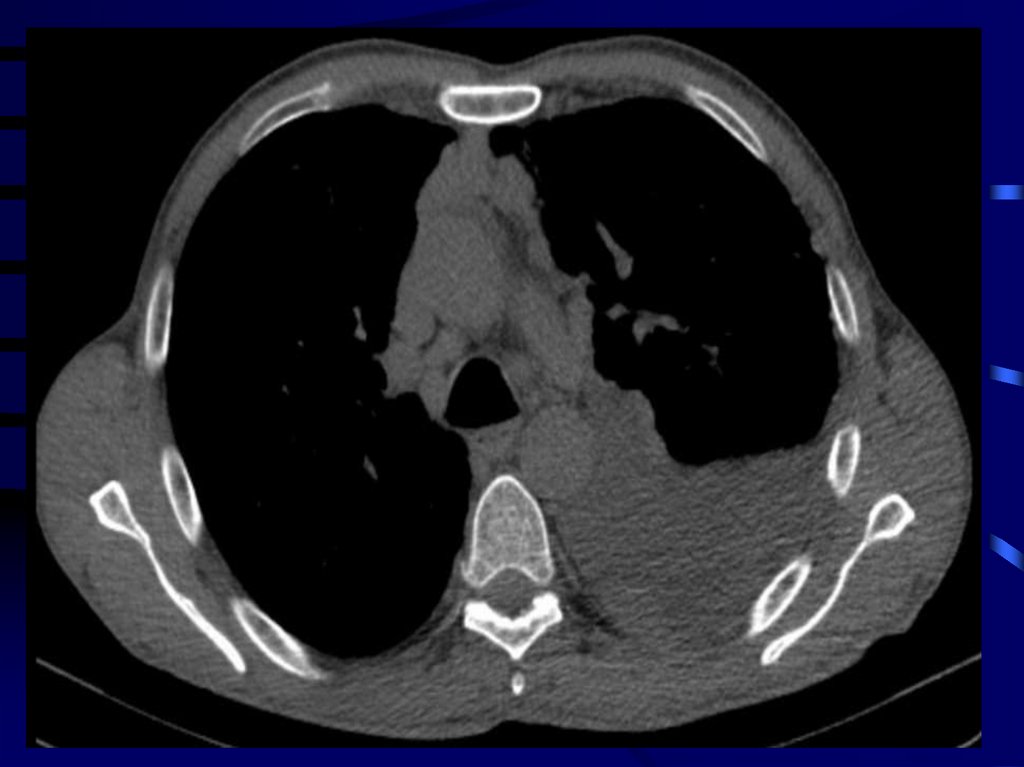

6. Обследование

Рентгенологическое исследование

Компьютерная томоргафия.

9.

• Опухоль ограничена париетальной и/или

висцеральной плеврой на одной стороне грудной

полости.